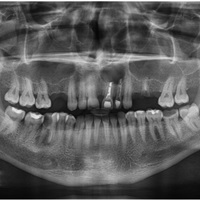

Pacjent z bólem, nieudana próba udrożnienia kanałów pod mikroskopem. Decyzja o resekcji korzenia policzkowego dalszego. RTG kontrolne rok po zabiegu.